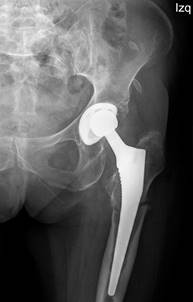

Controles: pacientes con diagnóstico de aflojamiento protésico, sometidos a cirugía de recambio, sin llegar a producirse fractura periprotésica (n = 19) (Figura 1).

Radiológicos: hallazgo en radiografías simples de radiolucencias progresivas de más de 2 mm en dos radiografías espaciadas al menos un año (describiendo su localización según las zonas de Gruen) (Figura 2). También se tuvieron en cuenta otros hallazgos radiológicos como el stress shielding, el fenómeno del pedestal, el desgaste del polietileno o el hundimiento del vástago. Por último, también incluimos pacientes con hallazgos incongruentes en radiografías simples, pero que mostraron signos de aflojamiento en otras pruebas complementarias radiológicas (resonancia magnética, tomografía computarizada y gammagrafía).